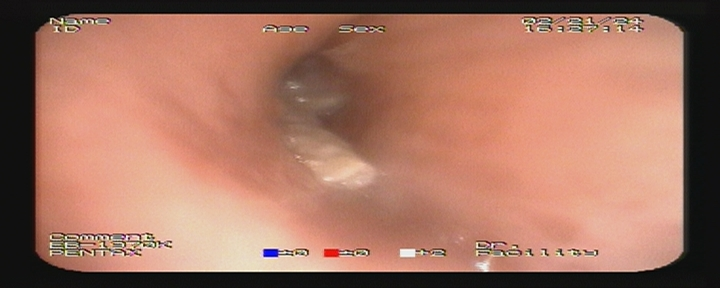

????2月21日,在漳州市中醫(yī)院氣管鏡室里58歲林大姐正在行全麻氣管鏡檢查。術(shù)中見(jiàn):右肺中間段遠(yuǎn)端見(jiàn)一尖銳的扁長(zhǎng)形異物附著,周邊肉芽腫形成,行異物鉗夾出后,見(jiàn)一3×12mm異物。導(dǎo)致林大姐5年頑固咳嗽元兇找到了。

右肺中間段支氣管異物

取異物

異物取出后

右肺支氣管異物